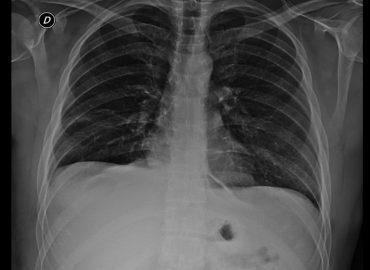

Paciente masculino de 57 años, dolor abdominal. AEA: Traumatismo